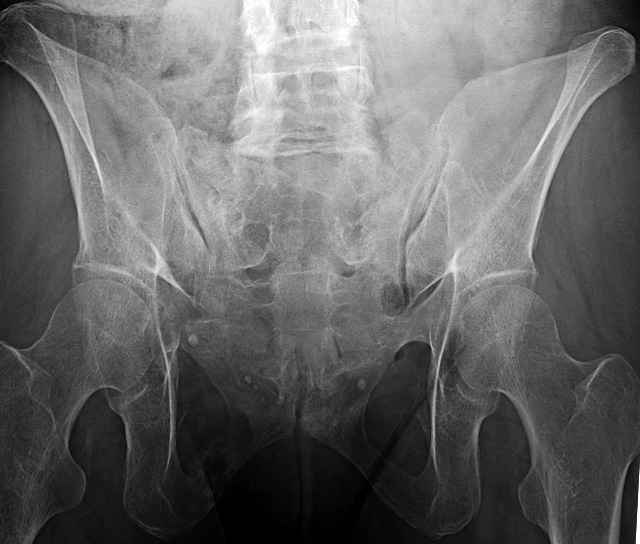

54 yo Female Fell c/o Pain

Initial Films

?Instability on Exam - Limited by Pain

NonOp Initial Mgmt